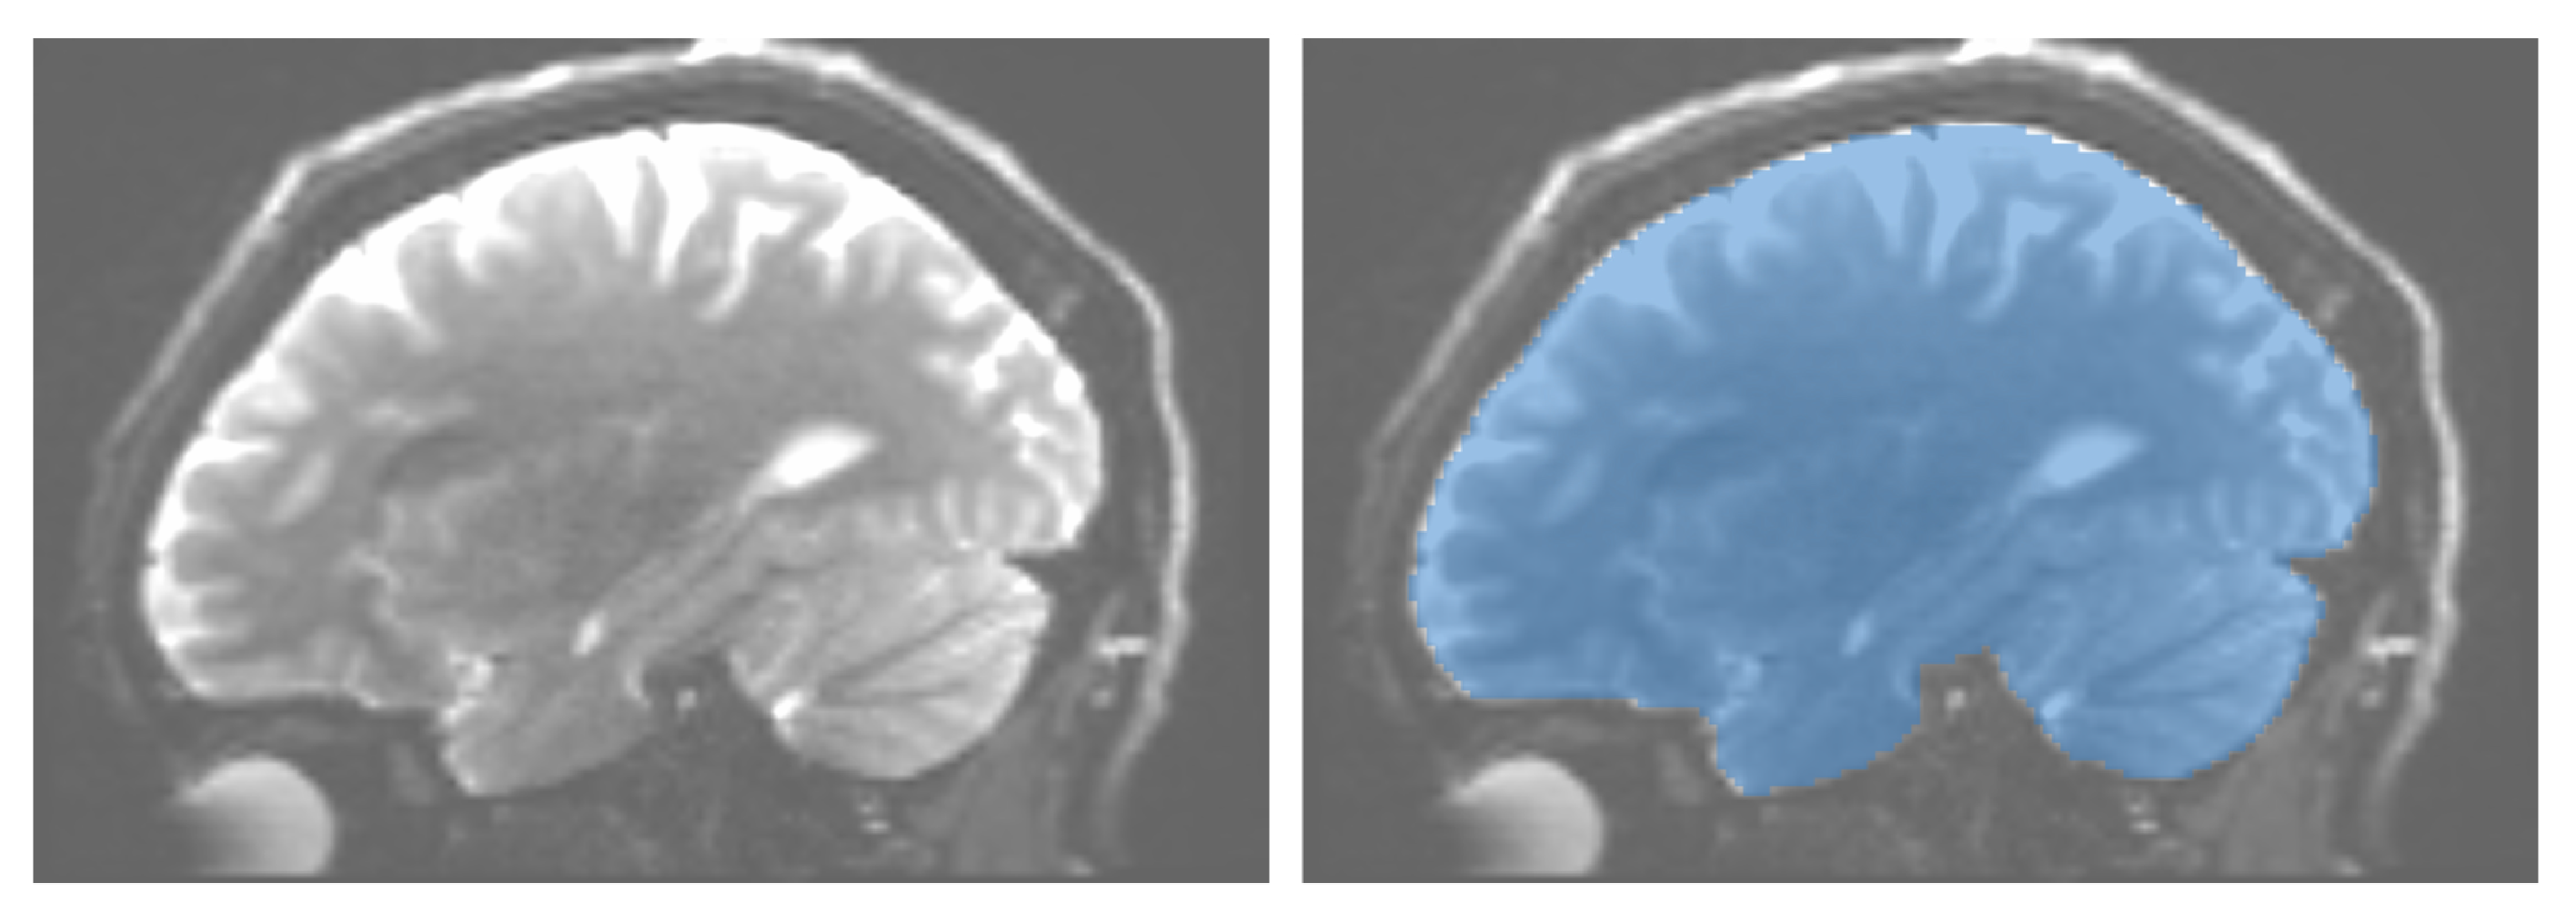

To start with, we need to construct the actual 3D trails representing streamlines in the major DTI eigenvector e 1 . The standard method to seed such streamlines is to look at regions M V of so-called high anisotropy, i.e., points x V for which the diffusion is far stronger in one direction than in all others. M can be computed by finding high-anisotropy voxels in V, i.e., points where the eigenvalues λ 1 , , λ 3 strongly differ [46]; alternatively, M is readily provided by so-called masks, suitably segmented from V by medical professionals based on their knowledge of fiber-rich versions [47]. The masks M we use in all our work are of the latter type, and they are provided with the public DTI datasets we use in our experiments [48,49,50]. Figure 1 shows such a mask for one of the datasets used in our work.